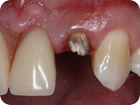

Retratamento Endodôntico

Retratamento Endodôntico 3